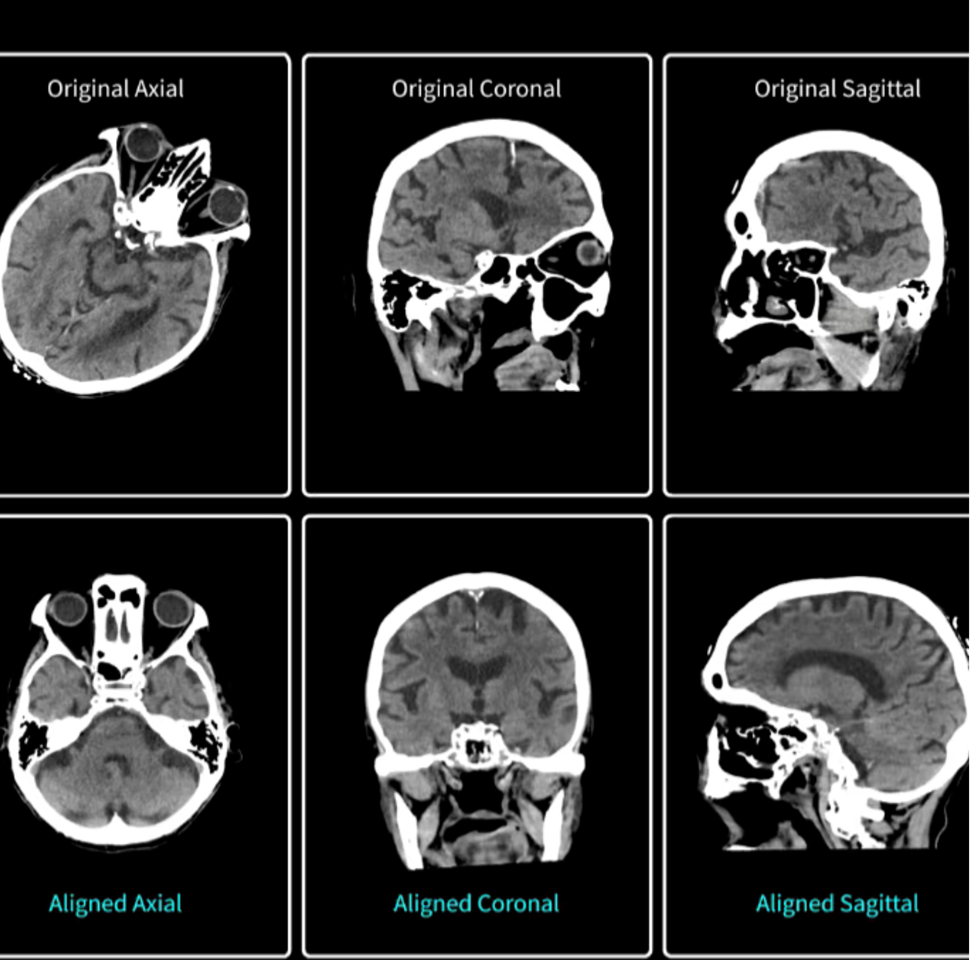

4. Head Auto-View: Ten-Second Cranial Reformats for Emergency Care

Post-processing a head CT traditionally involves rotating the image stack until the orbits, skull base, and foramen magnum align with canonical axial, coronal, and sagittal planes. This is a manual step that can add several minutes to a stroke or trauma workflow when time is critical. Head Auto-View automates the task by locating stable cranial landmarks and re-orienting the entire volume in roughly ten seconds.

Head Auto-View enables a 90 percent plus accuracy for patients scanned in the supine position, with automatic generation of axial, coronal, sagittal, and 3-D reformats routed directly to predetermined DICOM destinations. By eliminating a time-consuming bottleneck, the software can trim precious minutes from “door-to-needle” intervals when every minute of brain perfusion counts.